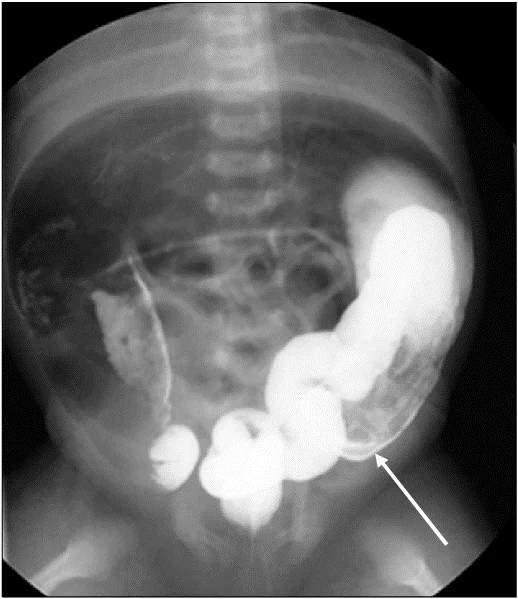

تشخیص HSCR بر اساس معاینه فیزیکی، سابقه کامل بیمار و خانواده، شناسایی علائم مشخصه و انواع آزمایشات تخصصی است. اکثر افراد (85-90 درصد) در اوایل دوران نوزادی تشخیص داده میشوند. اولین علامت معمولاً عدم دفع اولین حرکت روده (مکونیوم) است. تست تشخیصی ترجیحی برای HSCR بیوپسی ساکشنی رکتوم (suction biopsy of the rectum) است. بیوپسی شامل بریدن نمونه کوچکی از بافت آسیب دیده و مطالعه آن در زیر میکروسکوپ است. عدم وجود سلولهای گانگلیونی تشخیص را تایید میکند.

آزمایشهای اضافی که میتوانند مورد استفاده قرار گیرند عبارتند از: اشعه ایکس شکم که میتواند وجود انسداد روده را نشان دهد، مانومتری آنورکتال (anorectal manometry) که شامل استفاده از بالونها و حسگرهای فشار برای ارزیابی سلامت و عملکرد رکتوم و کنتراست یا تنقیه باریم است که شامل استفاده از ماده حاجب در رکتوم است.

ماده حاجب (contrast agent) ماده ای است که برای بهبود نحوه ظاهر شدن یک ساختار یا بخشی از بدن در عکس اشعه ایکس استفاده میشود. پس از استفاده از تنقیه کنتراست در راست روده، اشعه ایکس برای ارزیابی سلامت و عملکرد روده بزرگ گرفته میشود.